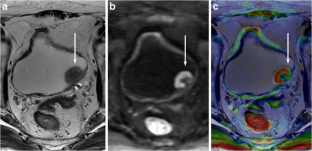

Fig. 3